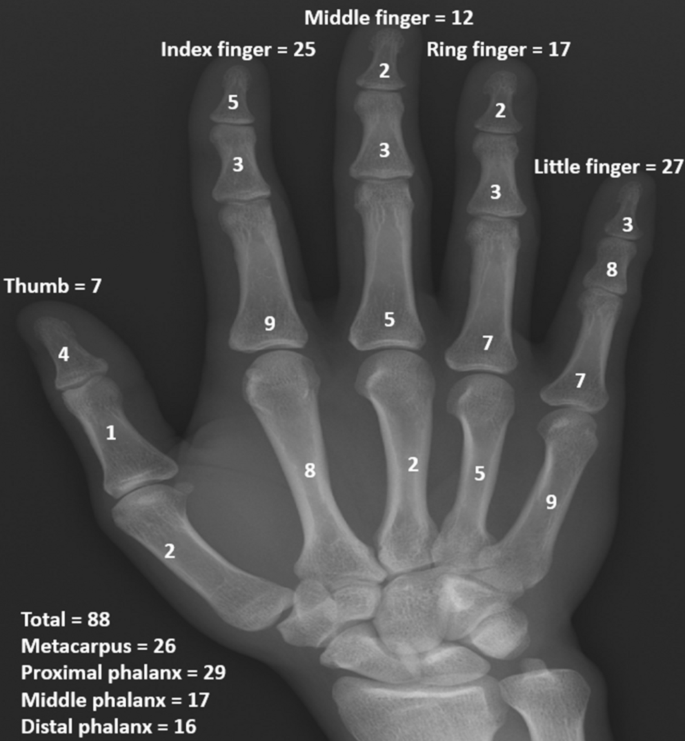

Proximal phalanges were most frequently affected, followed by metacarpal bones, mid-phalanges, and distal phalanges. The most common affected sites among the fingers were the index finger and the little finger (Fig 1). Mean long axis of the lesion was 15 mm (range, 6–35 mm). The mean radiological consolidation period was 6 weeks (range, 4–12 weeks). There were 23 (26.1%) patients with Takigawa type A, 35 (39.8%) patients with type B, 21 (23.9%) patients with type C, and 9 (10.2%) patients with type D. The difference in time for radiological consolidation according to the Takigawa classification was not significant (p = 0.166) (Table 1) (Figs 2 and 3).